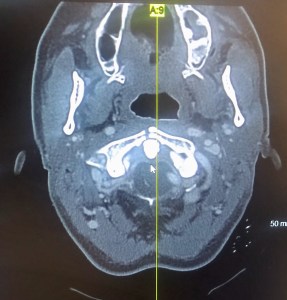

After fentanyl for the pain, a head CT, a CT angiogram to check the integrity of my carotid arteries and tons of blood work, the doctor came back to deliver the verdict in a solemn voice; there was no evidence of spinal cord damage or brain swelling but I had fractured the C1 vertabrae. As he was speaking, a smile began creeping onto my face. I then asked him, ‘are you saying I broke my neck?’ In a calm serious voice he responded, yes. To which I burst out into hysterical laughter! Of course I did! Leave it to me, it’s always got to be something – this time I stepped it up a notch! The doctor stared at me a moment, glanced at my husband, then responded, ‘I’ve never gotten that reaction before.’ A phone consult with the neurosurgeon in Oahu resulted in a discharge. By the grace of God I did not yet need surgery. I would need to wear a super spiffy neck brace for 5 weeks and return for a repeat CT. The craziest part of all? I would only need to take a week off of work! I had already taken a week vacation for my friend’s visit so I would only need to use a couple sick days, thereby leaving my sick leave stash barely touched for my pancreas transplant! (More on that another time.)